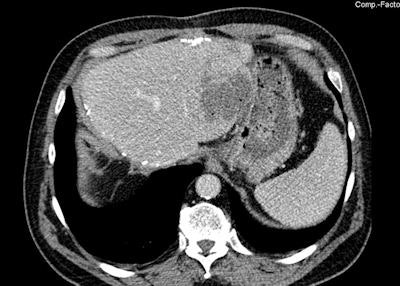

Above: MRI of an active liver metastasis near the gastric wall (parts of the liver had already been surgically removed two years previously). Below: Three IRE probes surround the tumor. Bottom: Signs of a tissue-sparing destruction of the liver metastasis in the CT review after the procedure.Images courtesy of Dr. Christian Stroszczynski, Regensburg University Hospital.

"This process is equivalent to an induced natural cell death, apoptosis," he said. "Whereas with thermal ablation procedures, for instance, the heat impact also involves the neighboring tissue, there is much less effect on the 'extracellular matrix,' as it is called, which surrounds the cell as a more stable tissue framework, and this usually recovers completely. This especially concerns blood vessels and lymphatic vessels and the nerve pathways. IRE does not induce the tissue necroses, which we have to accept with procedures that involve heat."